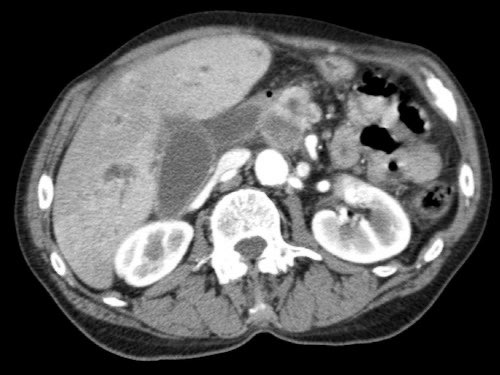

Dấu hiệu giọt nước mắt. Khối u lớn ở thân tụy, tiếp xúc 90 – 180 độ với SMV, đồng thời gây biến dạng SMV thành hình giọt nước mắt, rất nghi ngờ xâm lấn.

- Dấu hiệu giọt nước mắt (Teardrop sign)

Chỉ sự thay đổi hình dạng của tĩnh mạch cửa (PV) hoặc SMV từ hình bầu dục hoặc tròn sang hình giọt nước mắt. Điều này có thể do khối u bao quanh hoặc do xơ hóa lân cận kéo căng mạch máu. - Bất thường bờ viền mạch máu